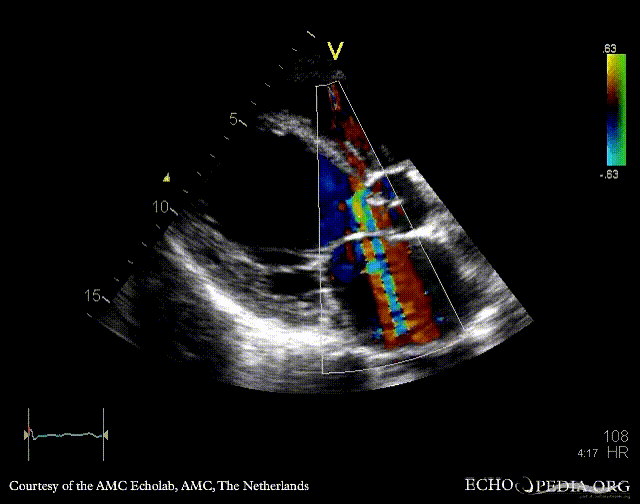

PLAX with Color Doppler: severe aortic regurgitation A4CH: dilated atria and ventricles, poor function of left ventricle